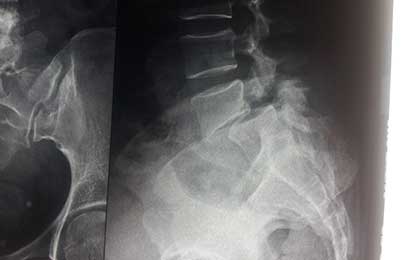

L5 S1 DEG LYSIS LISTHESIS

Spine Fixation Lumbar Spine